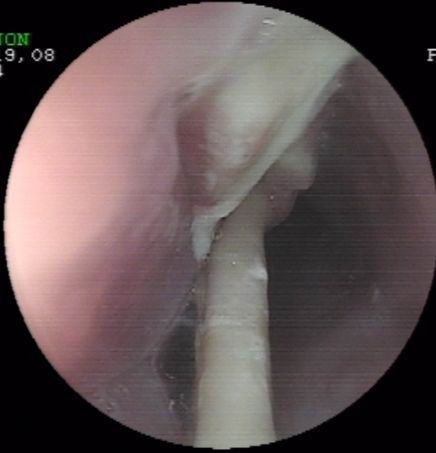

上個(gè)月末,一誤食異物(雞骨)胸骨后疼痛4天的患者經(jīng)胃鏡檢查確診為食管異物嵌頓。因患者異物嵌頓時(shí)間長(zhǎng),且患者其間還采取了其它一些清除異物的方法,造成異物的兩端均刺入食管壁,刺入處食管粘膜糜爛,充血,腫脹。按常規(guī),該患者應(yīng)收治外科行開胸手術(shù)取出術(shù),但患者家境貧寒,且為家里主要?jiǎng)诹?,無(wú)法承受醫(yī)療費(fèi)用及開胸術(shù)后所造成暫時(shí)的勞動(dòng)能力降低的損失。為減輕患者經(jīng)濟(jì)負(fù)擔(dān)及痛苦,在確診食管異物尚未造成食管周圍重要臟器損傷的情況下,該室決定在胃鏡下試取,經(jīng)多方面嘗試,最終成功將一長(zhǎng)約3.6cm兩端鋒利的雞骨(圖示)行內(nèi)鏡下取出,術(shù)后患者康復(fù)好,真正做到了微創(chuàng)手術(shù)解除患者大問(wèn)題,減輕了患者經(jīng)濟(jì)及軀體負(fù)擔(dān)。